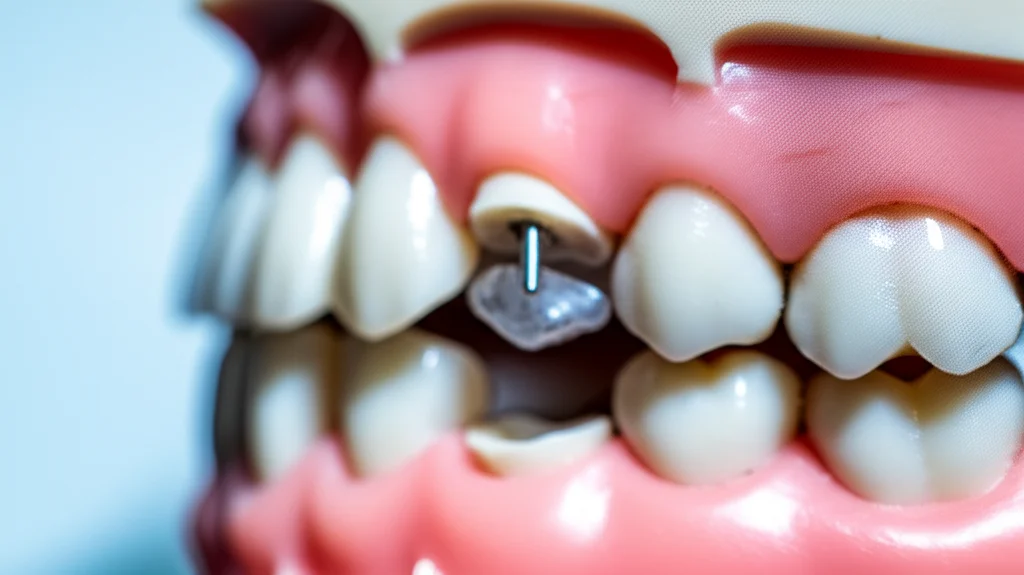

Ma l’apparecchio da solo non bastava. Per realizzare i movimenti complessi necessari – spostare indietro (distalizzare) tutta l’arcata superiore e la parte destra dell’arcata inferiore, e contemporaneamente spostare avanti (mesializzare) la parte sinistra dell’arcata inferiore – avevamo bisogno di un ancoraggio solidissimo. Ecco che entrano in scena le miniviti ortodontiche (o miniscrew). Ne abbiamo inserite strategicamente: due nel palato, tra i molari superiori, una sulla mandibola a destra (nella cosiddetta “buccal shelf”) e una tra canino e secondo premolare inferiore a sinistra. Queste piccole viti in titanio, inserite nell’osso con una procedura minimamente invasiva, fungono da punti di ancoraggio fissi, permettendoci di applicare forze precise senza effetti collaterali indesiderati sugli altri denti.

Il trattamento è iniziato con l’applicazione dell’apparecchio linguale, realizzato su misura grazie a mascherine di trasferimento stampate in 3D. Abbiamo usato una sequenza di archi ortodontici sempre più rigidi per allineare e livellare i denti. Dopo circa un mese, sono stati estratti i denti del giudizio. Dopo cinque mesi, siamo passati ad archi in acciaio rettangolari e abbiamo inserito le miniviti.